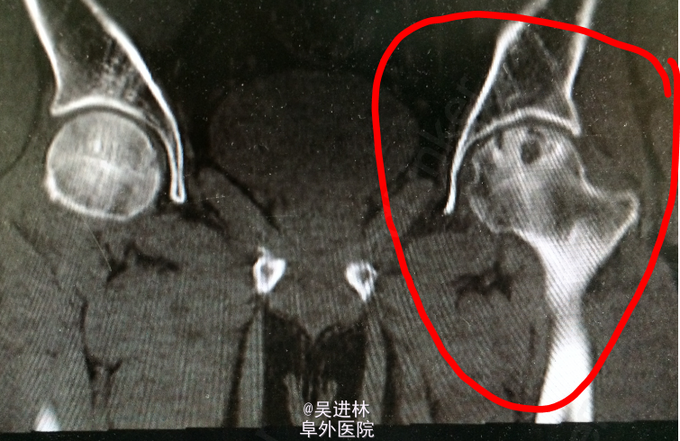

患者老年男性,主因“左髋部疼痛不适2年余”入院;查体:左侧腹股沟压痛+;活动度受限;4字试验+,托马斯征+;辅助检查:CT示左侧髋臼骨多发骨质破坏,累及周围软组织;全身骨显像示左髋臼窝核素浓聚灶;MIR描述如图。T-spot阳性!现在对于诊断基本持两种意见:因为患者病灶累及软组织,MRI上髂腰肌可见高信号,而且T-spot阳性,考虑TB。另外一种观点认为:病人除了T-spot并无其他TB征象,而且如果是TB的话,现在早就应该形成冷脓肿和窦道了,再者从MRI上来看,病灶呈膨胀性生长,边界清楚,所以考虑骨肿瘤可能性。what do you think?